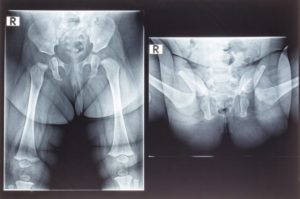

Рентгеновские снимки делаются в положении лежа, в двух состояниях – с выпрямленными ногами и с разведенными коленями врозь. На снимок должны попасть оба тазобедренных сустава для возможности поведения сравнения.

Для оценки снимка тазобедренных суставов доктор измеряет определенные углы и линии, которые «чертит» на рентгенограмме. Для начала проводят вертикальную линию через середину крестца. Далее – горизонтальную прямую через нижние точки подвздошной кости (линия Хильгенрейнера).

Перпендикулярно ей, по верхнебоковому краю вертлюжной впадины рисуют вертикальную линию (линия Перкина). Далее через края вертлужной впадины проводят касательную линию до пересечения с линией Хильгенрейнера. Полученный угол называется «ацетабулярным» и его оценка важна для выявления дисплазии.

У новорожденных его величина около 25 градусов и уменьшается с возрастом. В пять лет он составляет около 15 градусов.

Важную роль играют ядра окостенения головки бедренной кости, которые в норме появляются в среднем в 4-6 месяцев, в зависимости от пола ребенка. В норме они расположены ниже линии Хильгенрейнера и медиальнее линии Перкина.

Еще два важных параметра – величины “h” и “d”. Величина “h” показывает вертикальное смещение головки бедра – от линии Хильгенрейнера до середины головки. В норме она составляет 9-12 мм.

Величина “d” – это смещение латерального края головки бедренной кости относительно вертлужной впадины. Расстояние измеряется от дна впадины до середины величины “h”. В норме она составляет 15 мм.

Для этого на рентгенограмме делают разметку из нескольких линий:

- Вертикальную черту проводят через середину крестца.

- Горизонтальная черта Хильгенрейнера проходит по нижним краям подвздошных костей, которые хорошо визуализируются на рентгеновском снимке. Эти крупные кости образуют впадины для тазобедренных суставов.

- Через верхненаружные края подвздошной кости опускают перпендикуляр – черту Перкина.

- Вдоль краёв вертлужной впадины до горизонтальной черты проводят касательную линию. Образовавшийся угол называют ацетабулярным, или углом наклона крыши вертлужной впадины. По некоторым авторам он носит название угла альфа. В норме у новорождённых угол (α) наклона крыши вертлужной впадины 25–29°.

Возрастная норма угла при рентгене тазобедренных суставов у детей:

- 1 год жизни – у девочек 20°, мальчиков 18,4°;

- в 5-летнем возрасте – < 15°.

Увеличение угла наклона свидетельствует об отставании окостенения, а это означает степень суставной дисплазии.

В диагностике дисплазии тазобедренного сустава имеет значение показатель h – это расстояние от горизонтальной черты до середины бедра. В норме h=9–12 mm. Уменьшение величины указывает на дисплазию. Кроме того, определяют величину d – расстояние от дна вертлужной впадины до h. На нормальном снимке она 15 мм. Расшифровку снимка делает врач ортопед или рентгенолог.